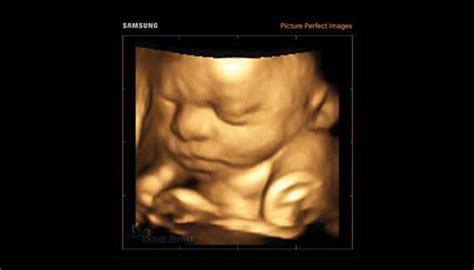

- Ecografie de sarcină de screening și avansată: Evaluarea detaliată a sarcinii pentru a detecta potențiale probleme.

- Screening trimestru 1 (săptămâna 11-13): Calculul riscului pe baza softului FMF, examinarea detaliată a fătului pentru diagnosticarea anomaliilor fetale majore și evaluarea riscului pentru trisomia 21 și alte anomalii cromozomiale.

- Screening morfologie fetală trimestru 2 (săptămâna 20-23): Examinarea detaliată a fătului pentru diagnosticul anomaliilor congenitale, incluzând hidrocefalie, spina bifida, malformații faciale, gastrointestinale și renale, tumori și chiste pulmonare, displazie osoasă și anomalii cromozomiale.